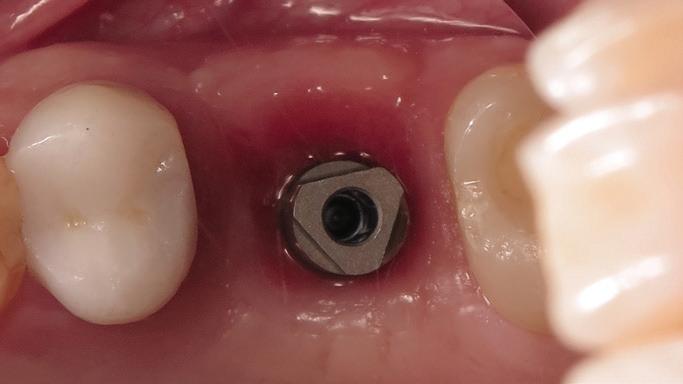

Tooth replacement from extraction to restoration. 3. Second-stage and impression procedures

The third part of this series reviews uncovering of implants that were buried in a 2-stage approach, provisionalization of the implant, and impression and scanning techniques.1 These techniques are all crucial for the final restorative outcome of the implant. The uncovering and second-stage procedures set the foundation for the shape and position of the soft tissue, which are very important esthetic factors. This information must also be properly transferred to the laboratory via a highly accurate impression so the laboratory has as much information as possible. If these steps are done properly, the result will be implant crowns that are easy to seat, biologically ideal, and esthetically pleasing.

Second-stage procedures